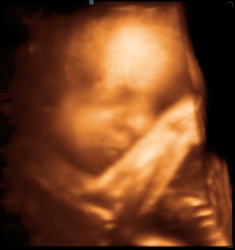

Уште едно заспано бебенце во стомакот на мама (3D)